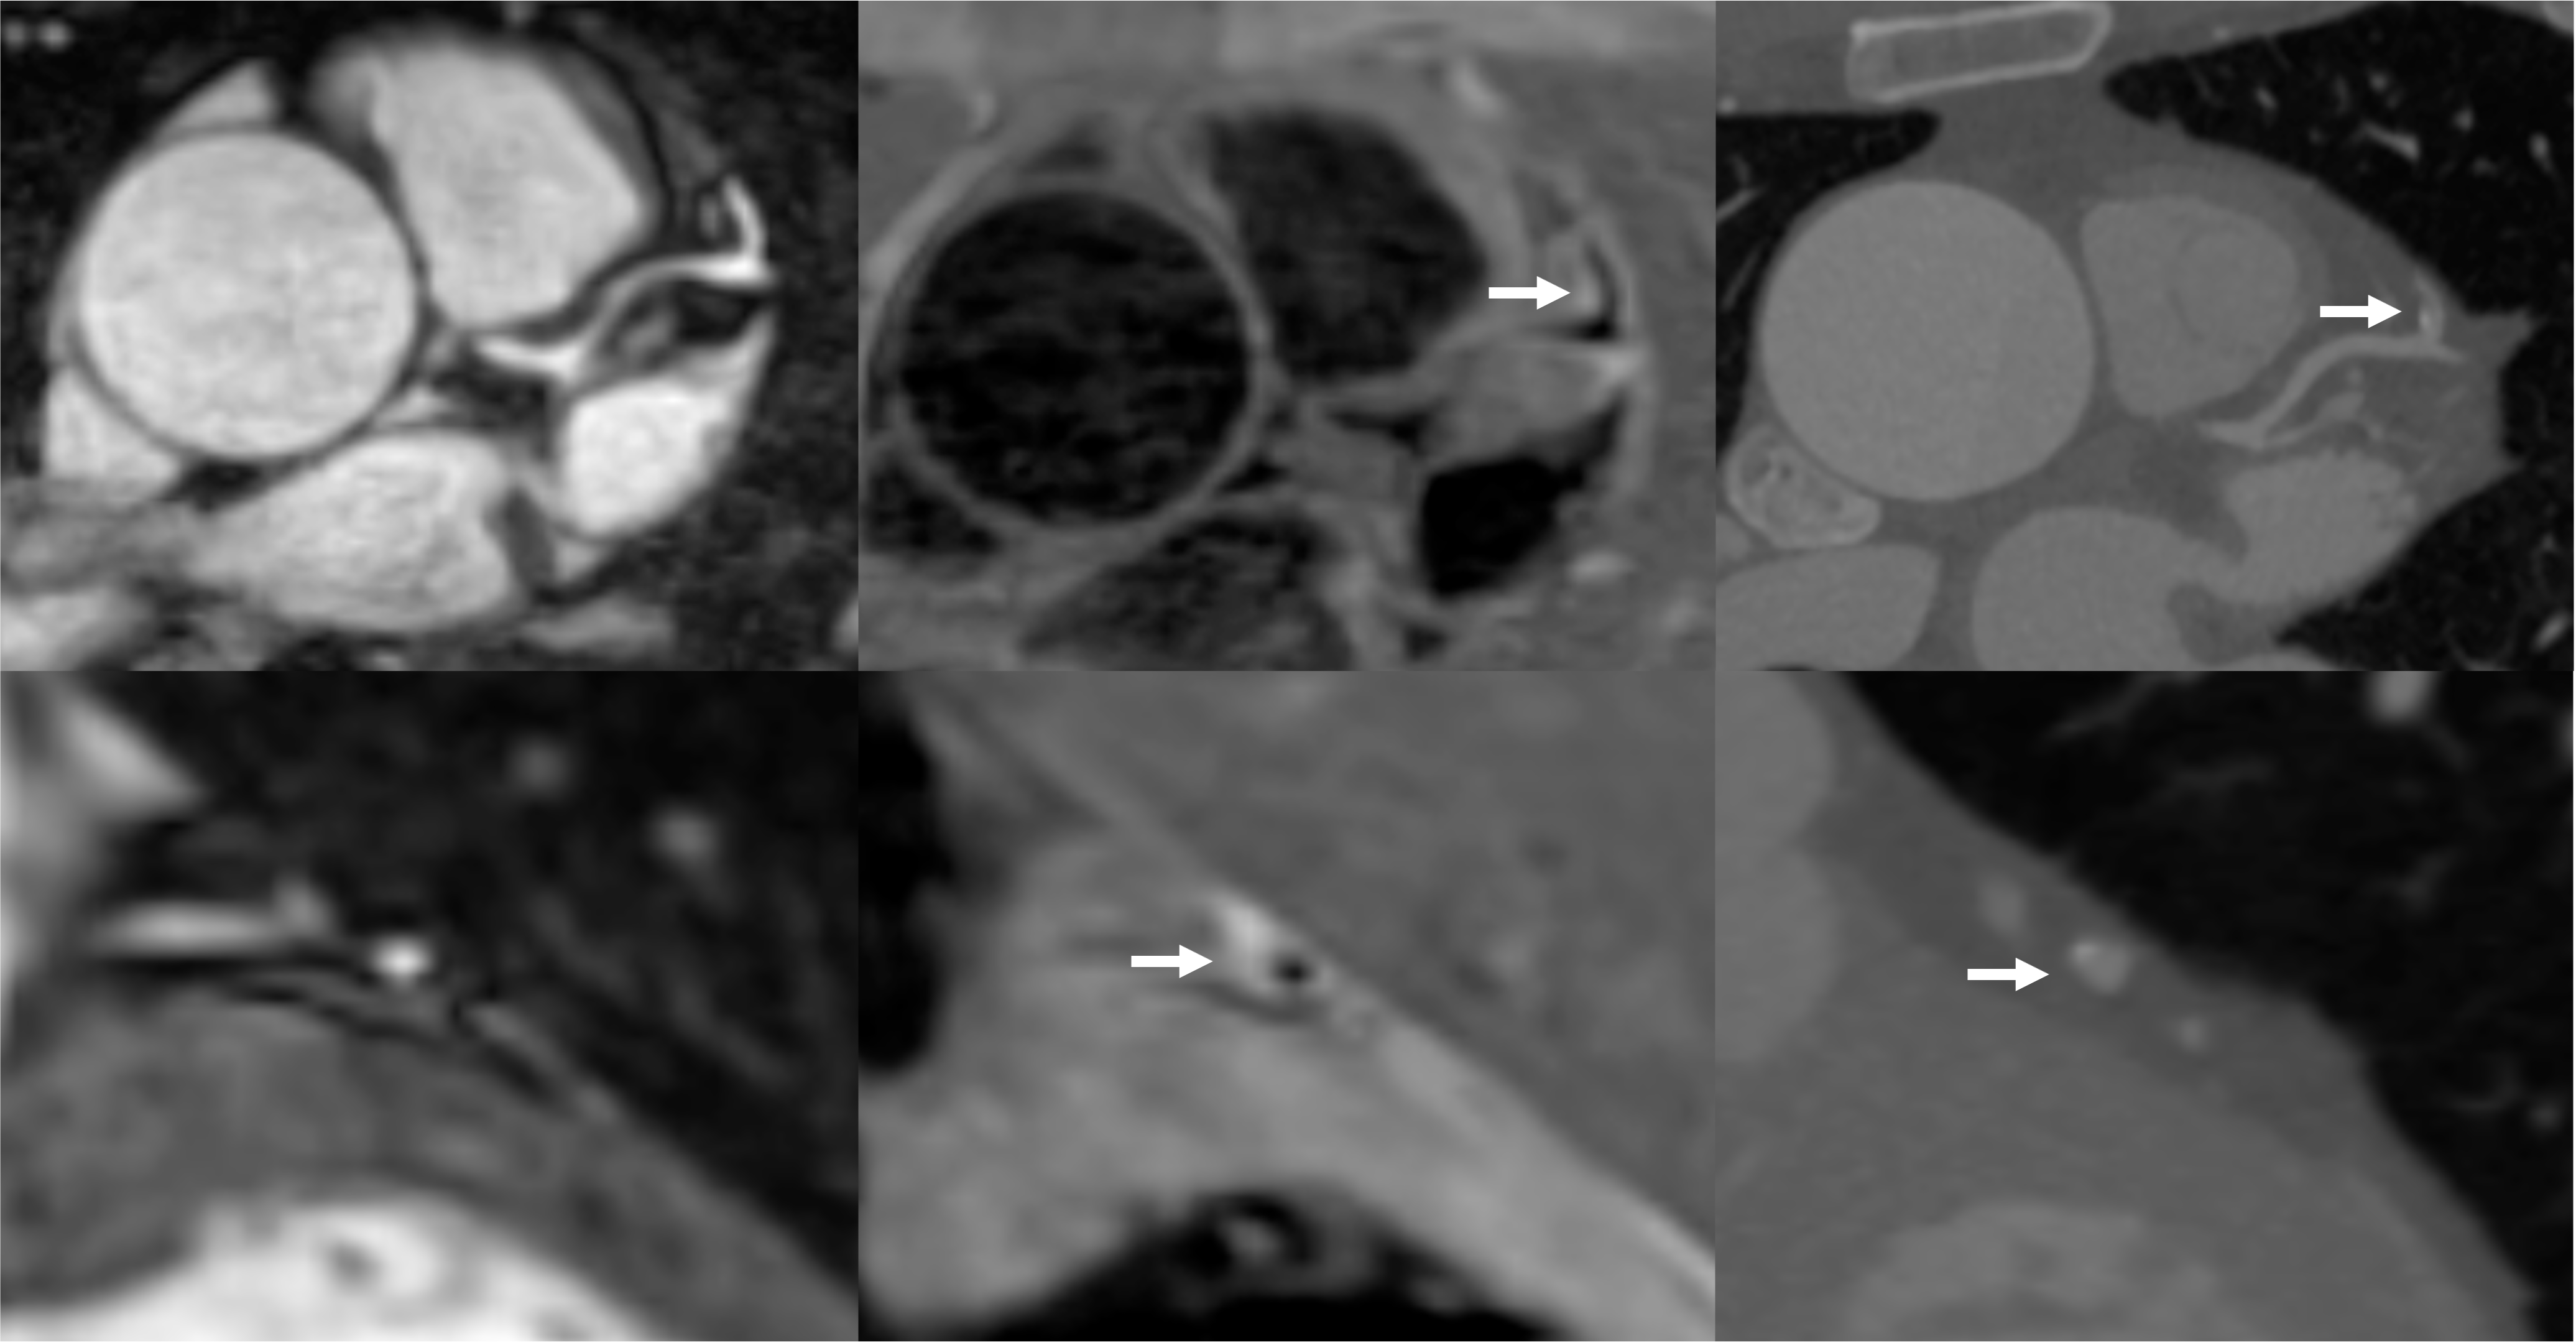

Figure 3. Paired comparison of PMR and healthy HVMR on iT2prep-BOOST (left) and Subgroup analysis of PMR across plaque morphologies and healthy vessels (right). Each red dot represents a single coronary plaque, with lines connecting paired PMR and HVMR values from the same patient. PMR values were significantly higher than HVMR values (mean difference = 0.28, p < 0.001), indicating increased signal in plaque regions relative to healthy vessel segments. Individual PMR values are shown for healthy vessels (blue), calcified plaques (red), mixed plaques (orange), and non-calcified plaques (green). A one-way ANOVA demonstrated a significant difference among groups (p < 0.001). Tukey’s post hoc test showed significantly higher PMR higher in all plaque types compared to healthy vessels (healthy vs calcified: mean difference –0.17, 95% CI –0.254= to –0.09, p < 0.001; healthy vs mixed: –0.35, 95% CI –0.42 to –0.27, p < 0.001; healthy vs non-calcified: –0.33, 95% CI –0.42 to –0.24, p < 0.001). Both mixed and non-calcified plaques showed significantly higher PMR than calcified plaques (mean difference –0.17, 95% CI –0.27 to –0.08, p < 0.001 and mean difference –0.16, 95% CI –0.26 to –0.05, p < 0.001, respectively). No significant difference was observed between mixed and non-calcified plaques (mean difference 0.02, 95% CI –0.09 to 0.12, p = 0.98)..png)